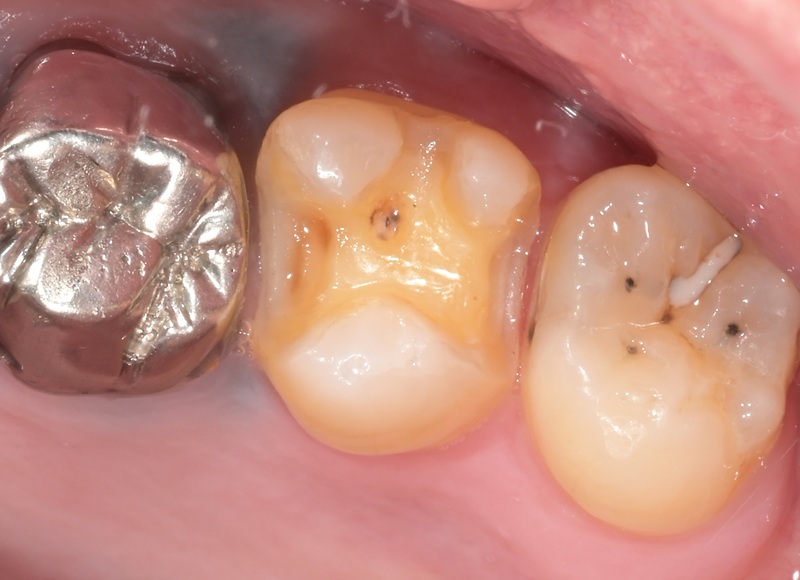

Case2

術前

術中

術後

| 治療名 | セラミックインレーによる虫歯の再治療症例 |

|---|---|

| 治療説明 |

過去に治療された銀歯が外れたとのことで来院されました。内部には古い接着剤の劣化と虫歯の再発が見られたため、しっかりと虫歯を除去し、セラミック製の詰め物(インレー)で再修復を行いました。 セラミックインレーは、天然歯に近い色調と自然な透明感を持っており、見た目が気になる部位にも適しています。 |

| 治療回数・期間 | 2回 |

| 副作用とリスク | ・保険診療の銀歯に比べて費用が高くなります。 ・治療直後は一時的に知覚過敏のような症状が出ることがありますが、ほとんどの場合は数日〜1週間程度で落ち着きます。 |

| 料金(税込) | 77,000円 |